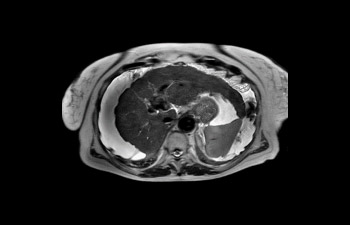

Hígado con ascitis